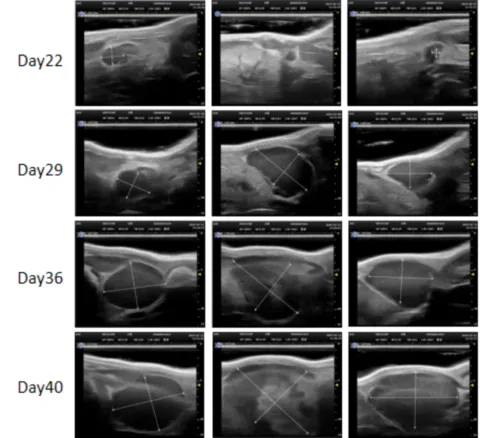

PDX Model (Growth Curve)

部分beats365PDX原位模型展示

部分beats365PDX原位模型展示